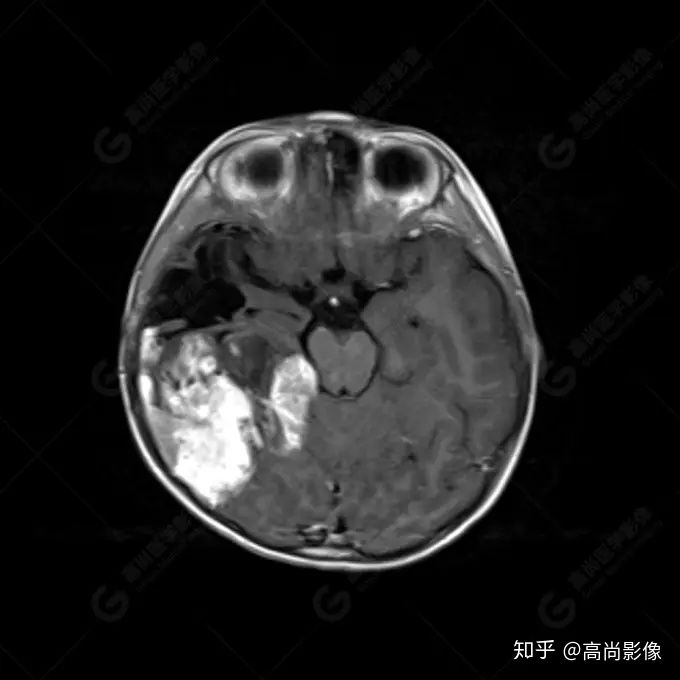

右側(cè)顳葉腫瘤切除術(shù)后(具體不詳):右側(cè)顳部骨質(zhì)不連續(xù)呈術(shù)后改變,右側(cè)顳葉術(shù)區(qū)見片狀長T1長T2信號影,F(xiàn)LAIR呈低信號;術(shù)區(qū)后方右側(cè)顳枕葉見一巨大占位性病變影,邊界欠清,大小約6.2×5.8×4.3cm(前后×左右×上下),信號不均勻,T1WI呈等稍低信號間雜少許高信號,T2WI呈高稍低混雜信號,DWI示部分病灶彌散受限,相應(yīng)ADC圖減低,磁敏感序列見部分呈極低信號,增強(qiáng)掃描可見明顯不均勻強(qiáng)化,鄰近硬腦膜及小腦幕增厚并明顯強(qiáng)化;另延髓右前方及右側(cè)橋小腦角區(qū)見一不規(guī)則形異常信號影,大小約3.2×1.3×3.7cm(左右×前后×上下),呈長T1稍長T2信號,F(xiàn)LAIR呈等信號,DWI未見受限,增強(qiáng)后明顯均勻強(qiáng)化,鄰近腦膜明顯強(qiáng)化。鄰近腦實質(zhì)及右側(cè)顳角明顯受壓;左側(cè)大腦半球未見局灶性信號異常,中線結(jié)構(gòu)稍左移。

右側(cè)顳葉腫瘤切除術(shù)后:現(xiàn)術(shù)區(qū)后方右側(cè)顳枕葉及延髓右前方占位,右側(cè)顳枕部硬腦膜及小腦幕明顯強(qiáng)化,結(jié)合既往影像資料,考慮為胚胎源性惡性腫瘤,如非典型畸胎樣/橫紋肌樣瘤(AT/RT)或原始神經(jīng)外胚層腫瘤(PNET)。